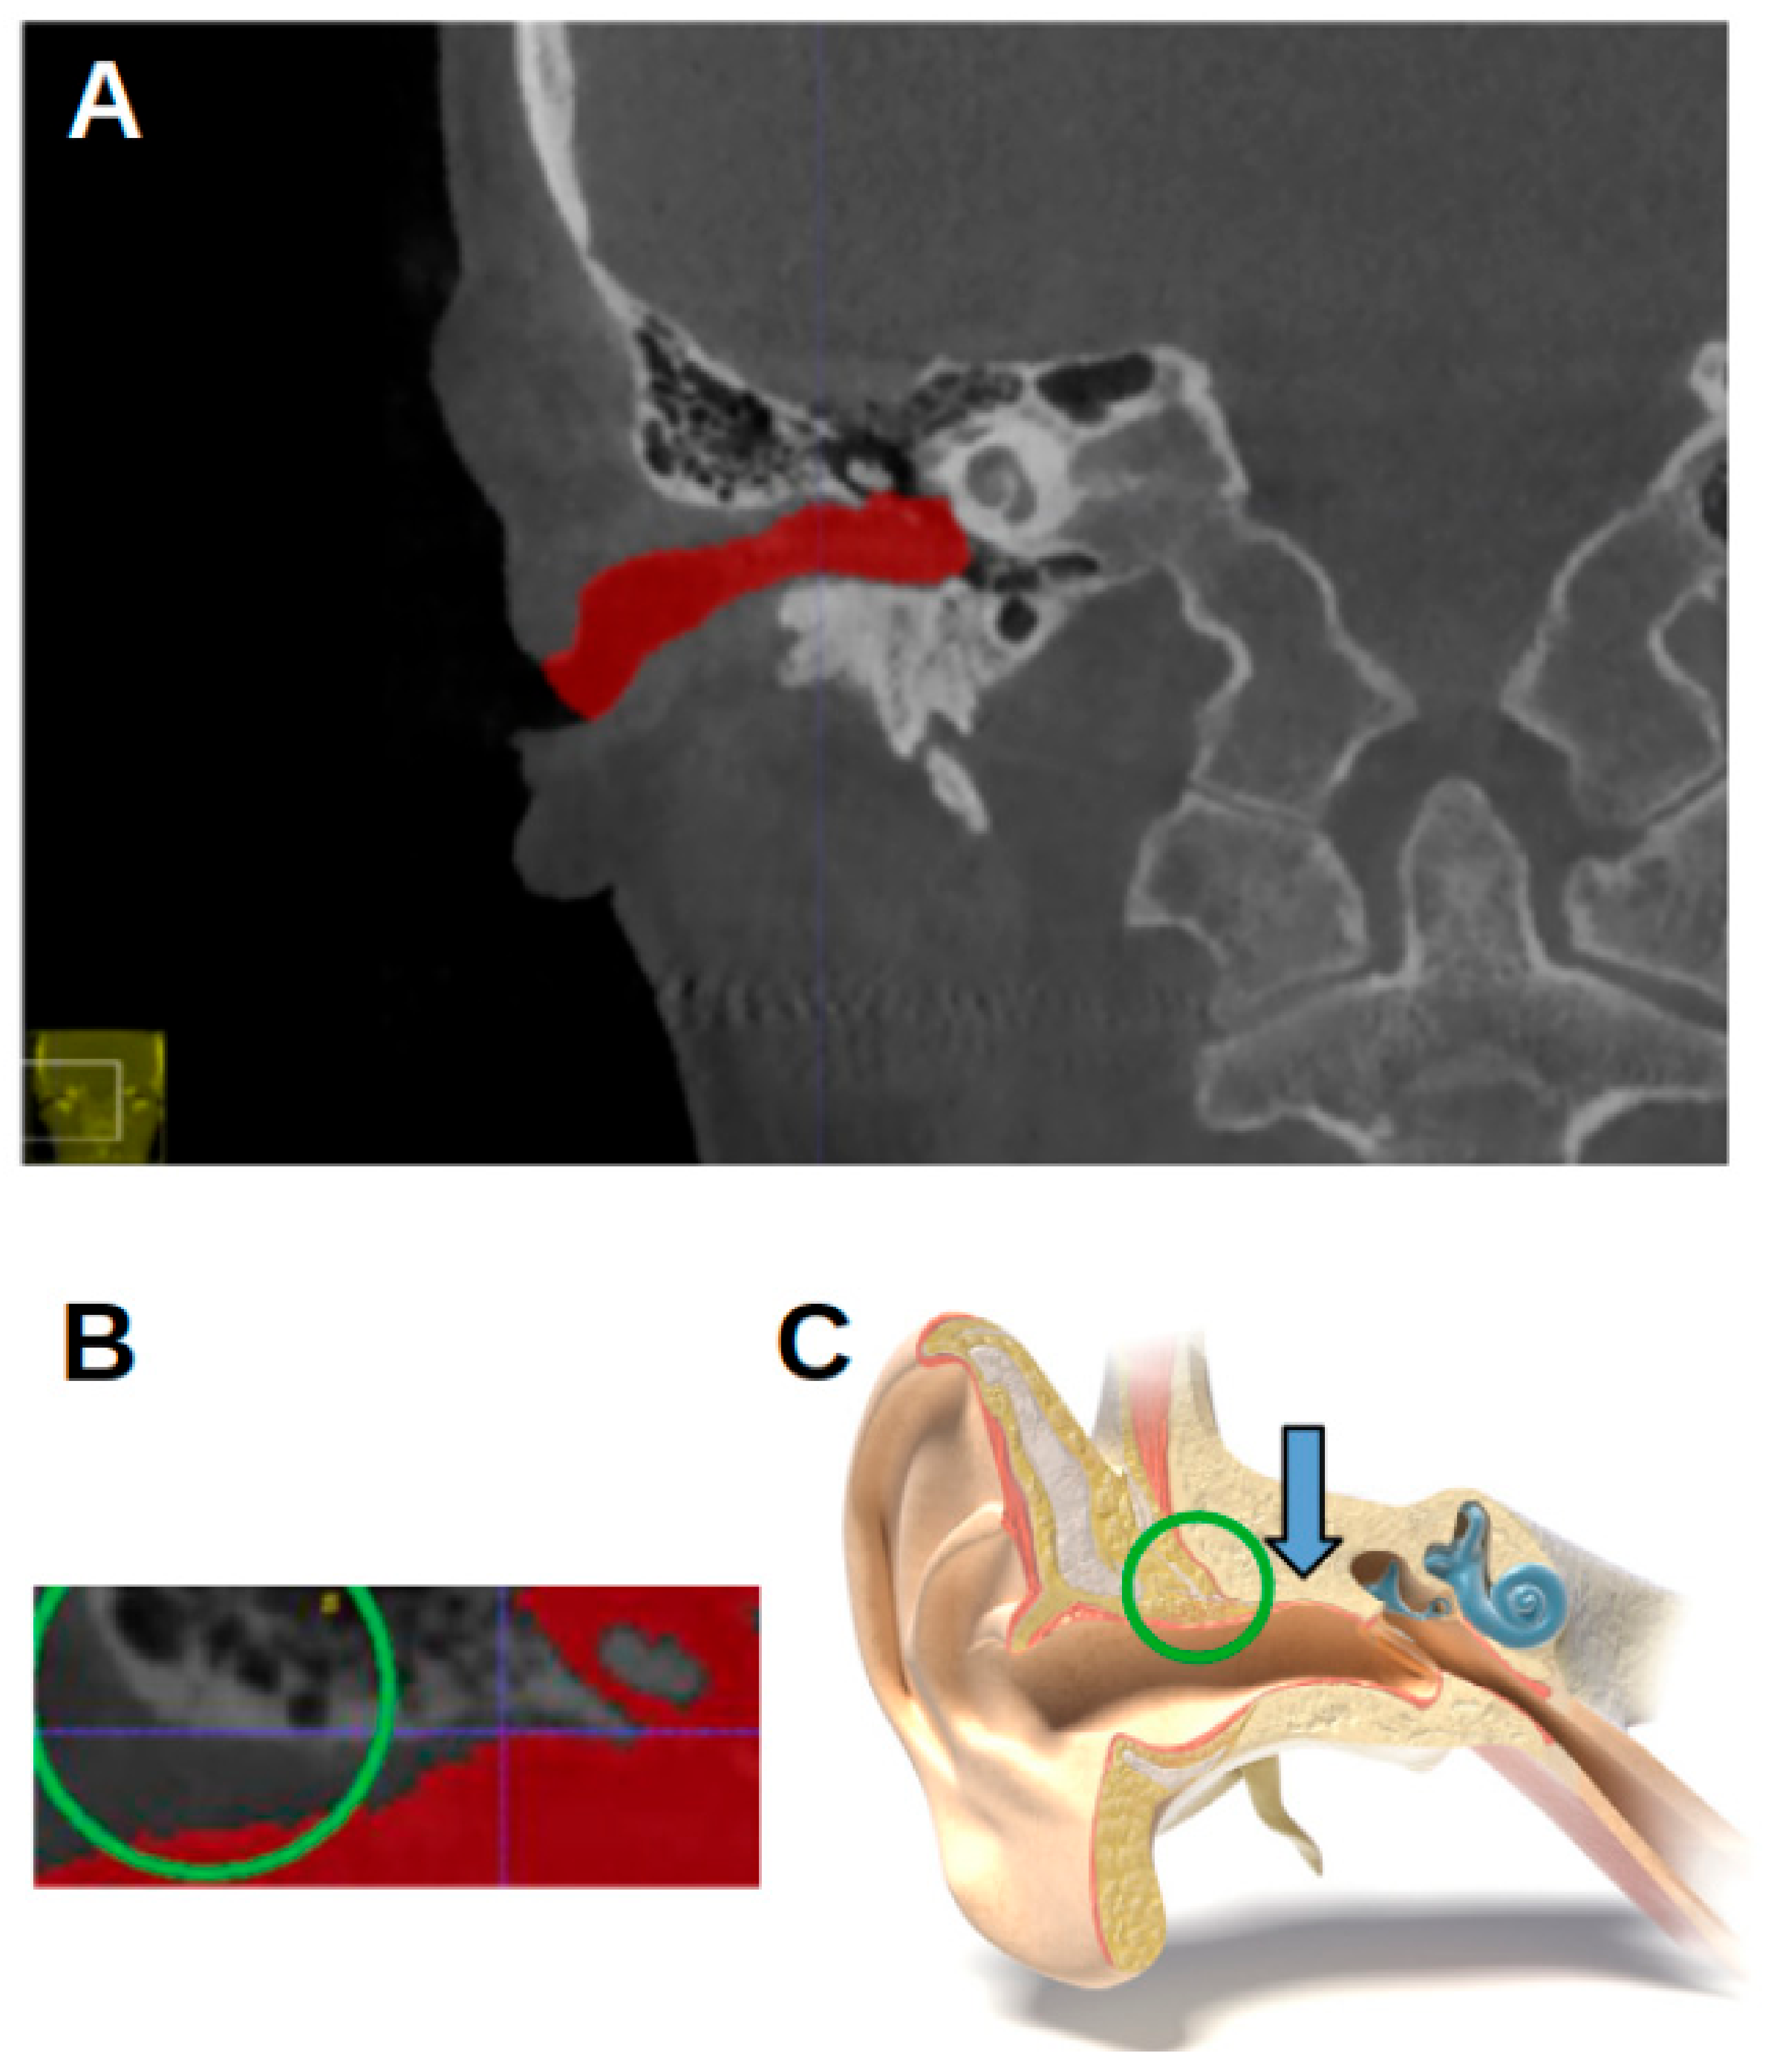

Per individual, five landmarks were established in the left and right external acoustic meatus: the most anterior point (MAP); the most posterior point (MPP); the most superior point (MSP); the most inferior point (MIP); and the notch-like rim between the innermost portion of the EAM and the epitympanic recess. As this has no official name, it is referred to as the epitympanic notch (EN) (Figure 2). Angular structures were sought because they might be easier to reproduce [16].

Figure 4 shows the most anterior and the most posterior point, marked with a white circle and a pink circle, respectively. Figure 5 shows the most superior and the most inferior point, marked with a blue circle and a yellow circle, respectively. In Figure 2, the EN is indicated by a red arrow.

Figure 2. The location of the epitympanic notch. (A) A CBCT image of a right acoustic meatus in a coronal view. The red arrow indicates the epitympanic notch. (B) A cross-section through the external acoustic meatus (“MedicalGraphics–Drawing Ear anatomy–no labels” at AnatomyTOOL.org by www.MedicalGraphics.de; license: Creative Commons Attribution-NoDerivatives).